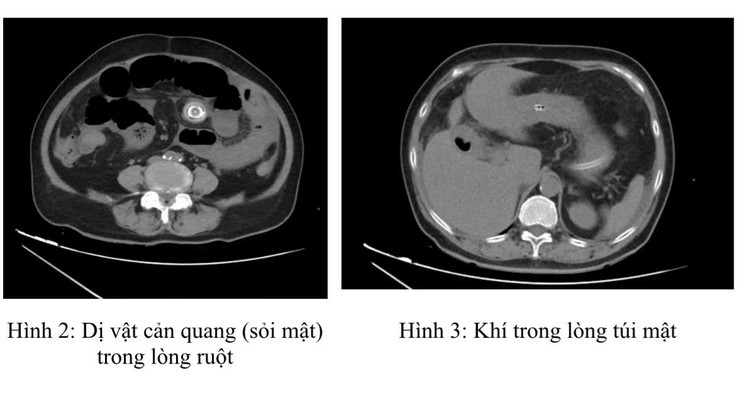

Chụp cắt lớp vi tính ổ bụng (CT scan) đã xác định rõ ràng tình trạng tắc ruột. Hình ảnh CT cho thấy giãn các quai ruột non quanh rốn kích thước 36mm có mức dịch khí, vị trí chuyển tiếp có dị vật cản quang hình tròn kích thước 23mm.

Đồng thời, túi mật thành dày nhẹ, chứa khí có đường thông với tá tràng. Đây chính là “bộ ba dấu hiệu Rigler” điển hình của tắc ruột do sỏi mật, bao gồm: hình ảnh khí trong đường mật (pneumobilia); tắc ruột non với mức nước-khí; và hình ảnh sỏi mật lạc chỗ trong lòng ruột.